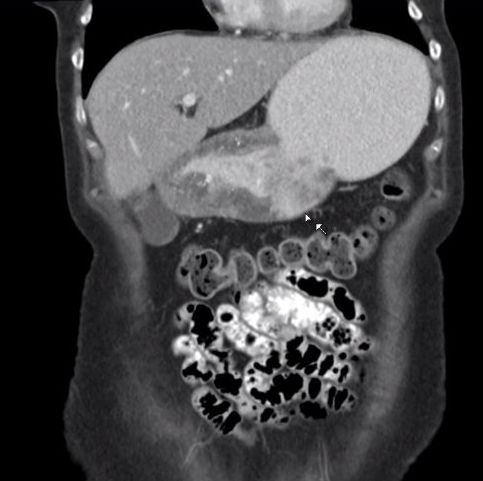

| Magenantrum | 54-jährige Frau mit obstruierendem Magenantrumkarzinom. ![]() |

|||